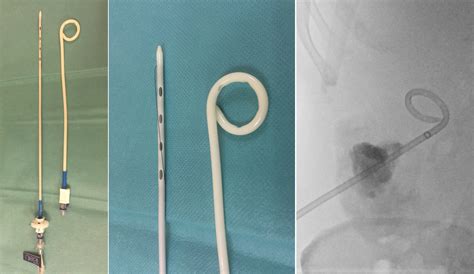

A Pigtail Chest Tube is a small, flexible tube with a coiled end that resembles a pigtail. This design allows for easier insertion and reduced trauma to the patient compared to traditional chest tubes. The tube is typically inserted using a Seldinger technique, which involves the use of a guidewire to facilitate placement. The primary function of a Pigtail Chest Tube is to drain excess fluid or air from the pleural space, thereby relieving pressure and promoting healing.

• Pigtail Chest Tube Placement: Insert the Pigtail Chest Tube over the guidewire and advance it into the pleural space. Remove the guidewire and secure the tube in place.